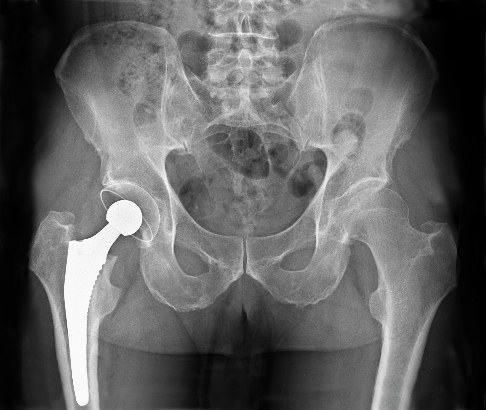

Die Behandlung erfolgt je nach Ursache. Oft reicht eine konservative Therapie aus, manchmal ist allerdings eine Operation nötig - z. B. kann bei fortgeschrittener Hüftgelenksarthrose der Einsatz einer Hüftendoprothese erforderlich werden.

Bei einer ausgeprägten Hüftarthrose ist häufig die Implantation eines künstlichen Hüftgelenks die Behandlung der Wahl. © Nicolas Larento, adobe

Operationen kommen dann infrage, wenn konservative Maßnahmen nicht ausreichen. Das trifft häufig auf eine fortgeschrittene Arthrose zu, bei der die Implantation eines künstlichen Hüftgelenks (Hüftendoprothese) empfohlen wird. Gleiches gilt für ein ausgeprägtes Hüftimpingement oder den Riss einer Gelenklippe - diese Erkrankungen werden allerdings meist im Rahmen einer Arthroskopie operiert.